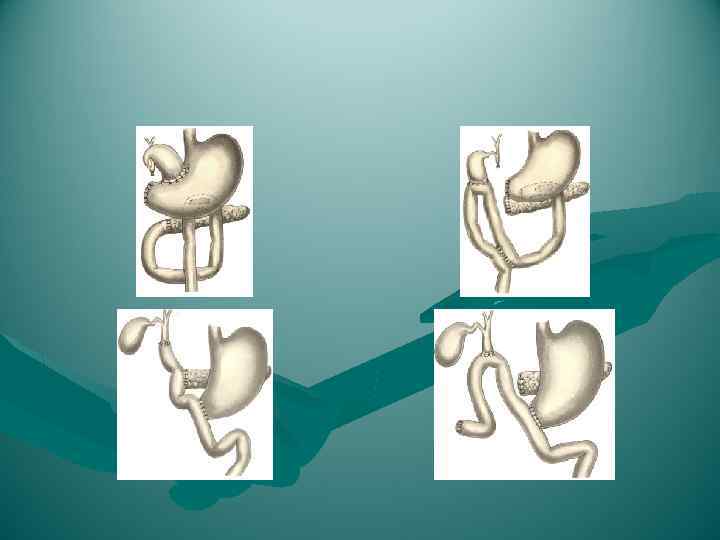

ВИДЫ ОПЕРАТИВНЫХ ВМЕШАТЕЛЬСТВ НА ПОДЖЕЛУДОЧНОЙ ЖЕЛЕЗЕ При панкреатитах - Рассечение капсулы и дренирование сальниковой сумки - при острых панкреатитах - Панкреатоеюностомия - при хронических панкреатитах, При раке поджелудочной железы - Тотальная панкреатодуоденэктомия - наиболее радикальная операция (удаляются pancreas, селезенка, антральный отдел желудка, двенадцатиперстная кишка) - Правосторонняя гемипанкреатикодуоденэктомия - при раке головки pancreas - Левосторонняя гемипанкреатэктомия - при раке хвоста pancreas, инсуломах

ВИДЫ ОПЕРАТИВНЫХ ВМЕШАТЕЛЬСТВ НА ПОДЖЕЛУДОЧНОЙ ЖЕЛЕЗЕ При панкреатитах - Рассечение капсулы и дренирование сальниковой сумки - при острых панкреатитах - Панкреатоеюностомия - при хронических панкреатитах, При раке поджелудочной железы - Тотальная панкреатодуоденэктомия - наиболее радикальная операция (удаляются pancreas, селезенка, антральный отдел желудка, двенадцатиперстная кишка) - Правосторонняя гемипанкреатикодуоденэктомия - при раке головки pancreas - Левосторонняя гемипанкреатэктомия - при раке хвоста pancreas, инсуломах

Резекция тела и хвоста поджелудочной железы.

Резекция тела и хвоста поджелудочной железы.